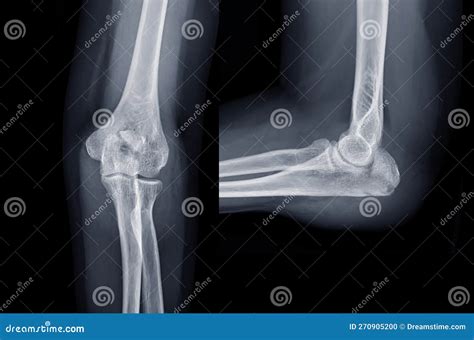

Ulna Bone Xray

1150 × 1262px January 10, 2026 Ashley

X-ray of Elbow Join Showing Fracture of Ulna Bone Stock Photo - Image ...

1600×1149